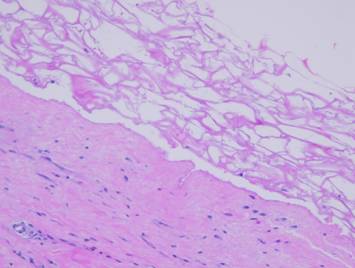

The second maturation process is the restoration of a normal epithelium.  Epithelium arrives on the wound surface in two ways – naturally by migration from wound margins or else by surgery (skin grafts).  Either way, the young closed wound typically has but a thin epithelium (epidermis in these examples).  After epithelial cells arrive, they reestablish a basal stratum germinativum.  As they resume their normal functions of keratinization and epithelial cell replenishment, maturation events can be seen.  Acanthocyte proliferation thickens the epidermis and leads to the formation of rete pegs as vascular tufts tile the subepithelium to maintain blood supply to the thickened lamina.  The metabolically active epidermis requires logistical support, so a lamina propria develops, the papillary dermis.  The deeper reticular dermis is a primary structure formed embryologically or in a regenerative biomatrix.  The papillary dermis is a secondary structure, engineered by the epidermis, which does not appear until epidermis has covered the wound.  The two dermal strata have distinctly different origins, purposes, and morphologies.

Right upper, young epidermis soon after a skin graft.  The epidermis is thin, the stratum germinativum is still immature, there is no papillation, and no specific or differentiated histo-morphology of the subjacent scar.  Right middle, a mature regenerated epidermis.  Normal acanthosis with rete ridges and mild superficial papillomatosis is present.  Blood vessels are present in each dermal papilla – these are the vascular tufts which supply the epidermis.  The dermal layer has two distinct tangential zones.  The upper layer is the papillary dermis, triggered by the overlying epidermis when it was placed on the underlying reticular layer.  The new papillary dermis is fairly normal in appearance - it may improve further with age, but it already looks like normal native papillary dermis.  The bottom reticular layer is NOT at all like normal reticular dermis.  It is the scar from the previous open wound.  It is cellular and has lamellated collagen which is dense and non-compliant, but with relatively thin collagen bundles compared to normal reticular dermis - i.e. it is scar.  Right lower, as epidermis matures, other normal features appear, such as Langerhans cells and, depending on the source of the new epithelium, melanocytes and melanin.  These are all innate features of the epidermis and epidermal-dermal interactions, and they occur independent of what had previously happened in the mesenchymal dermis or scar or wound module underneath.  Left, two panes showing maturation of epithelium after an ankle ulcer.  Left is a recently healed skin graft showing fragility, brittleness, accelerated desquamation, and inconsistency of the corneum.  Right is a view a year later when epidermis has returned to normality.  This maturation corresponds to the changes seen in the histology views.